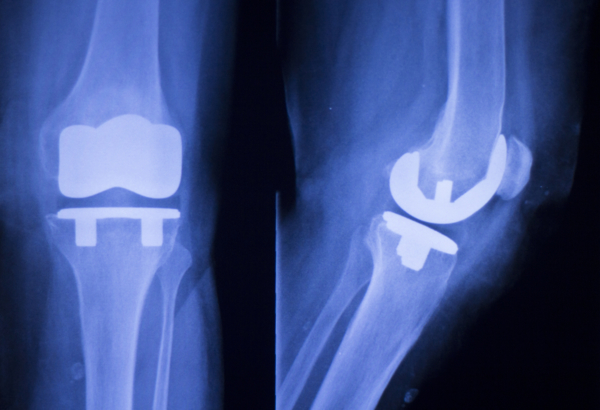

日前,俄罗斯技术国际集团(Rostec)的成员企业Shvabe股份公司开发了一种具有可设计生物力学性能的碳复合材料(CCM)人体植入物。

除了价格以外,与目前医疗界广泛使用的金属、陶瓷和聚合物植入物相比,碳复合材料植入体拥有一系列的优异性能。特别是,由于所有的人体组织都含有大量的碳,因此,碳复合材料植入物拥有更高的生物兼容性。